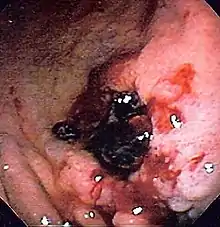

![]() Endoscopic still of esophageal ulcers seen after banding of esophageal varices, at time of esophagogastroduodenoscopy | |

Deep gastric ulcer